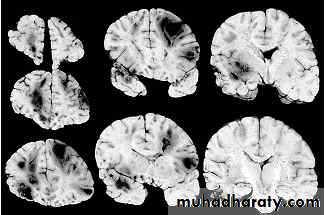

3. Brainstem and hemispheric (Cerebral) Contusion

These are areas of bruising and swellings with intact pia arachnoid, localized or generalized oedema and haemorrhage due to tearing of blood vessels.

3. Cerebral Contusion

Clinical presentations:

1. Prolonged periods of unconsciousness.

2. Focal neurological deficits that persist for longer than 24 hours.

CT scans demonstrates contusions as small areas of haemorrhage in the cerebral parenchyma.

Contusions may resolve with the accompanying deficits or they may persist.